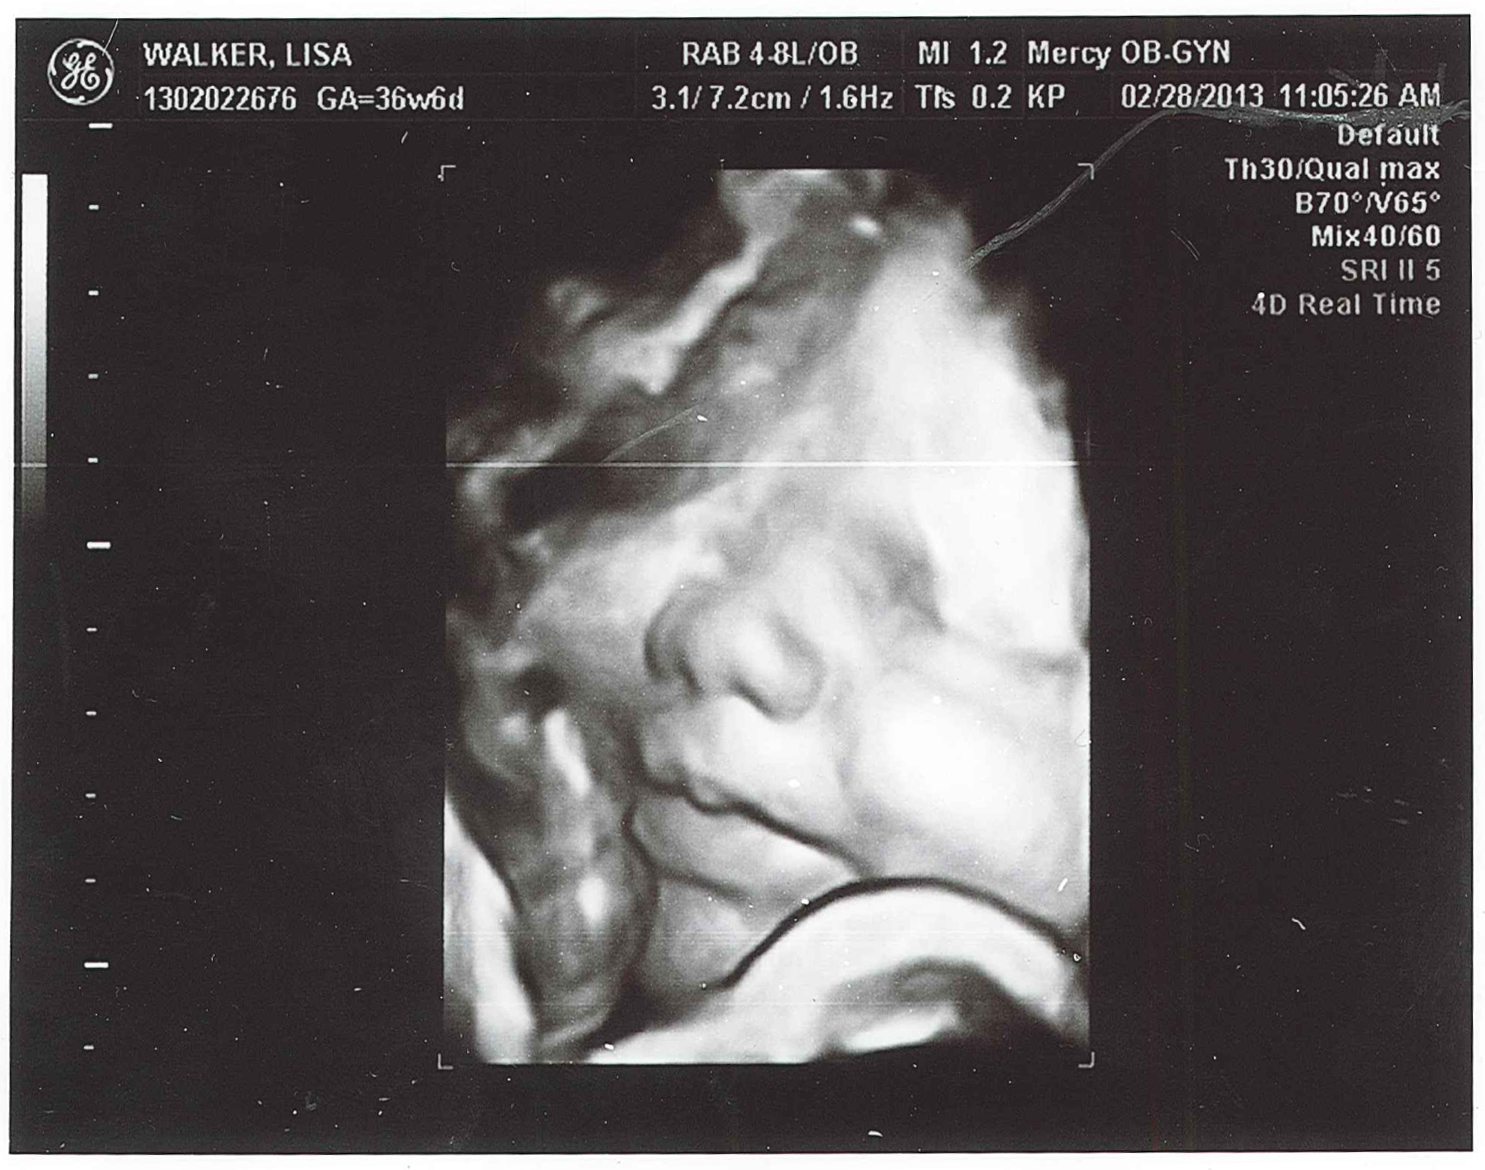

From walkerjeremy.blogspot.com

Pages From the Pursuit Photos Baby Boy Ultrasound at 37 weeks Why Is My Baby So Small At 37 Weeks Why is my baby small? If your baby is measuring smaller than the amount of weeks you are at, they are said to have a small gestational age (via the university of rochester medical center). Babies born weighing less than 5 pounds, 8 ounces are. Fetal growth restriction (fgr), formerly called intrauterine growth restriction (iugr), refers to a condition in. Why Is My Baby So Small At 37 Weeks.